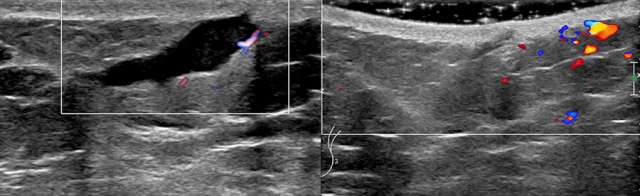

Case: Skin Lesion Figure 2

Figure 2. Targeted sonography of the left inframammary fold in a patient with history of breast reconstruction, demonstrates a resolving complex fluid collection with residual thin tract to the skin favored to represent an involuting epidermal inclusion cyst.